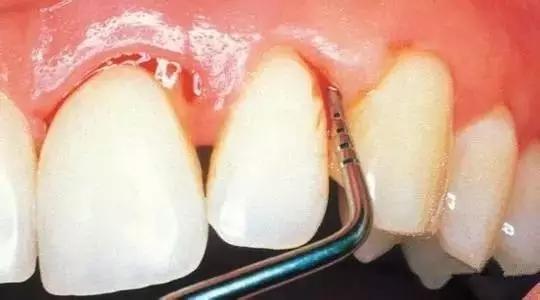

我们叫六龄牙,是四胞胎兄弟,在六岁左右的时候长出的第1颗恒牙,但是刚长出来的我们牙合面窝沟裂隙多,牙釉质很薄,很容易发生蛀牙,也不喜欢甜食,零食,所以主人一定要给我们穿上保护外衣【窝沟封闭】,若不好好保护我们,我们就要一步步走向毁灭了。

(窝沟封闭过程)